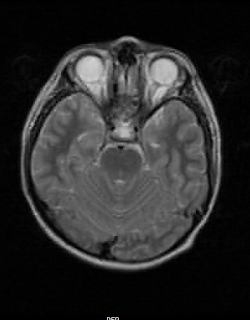

Septo-optic Dysplasia-MRI